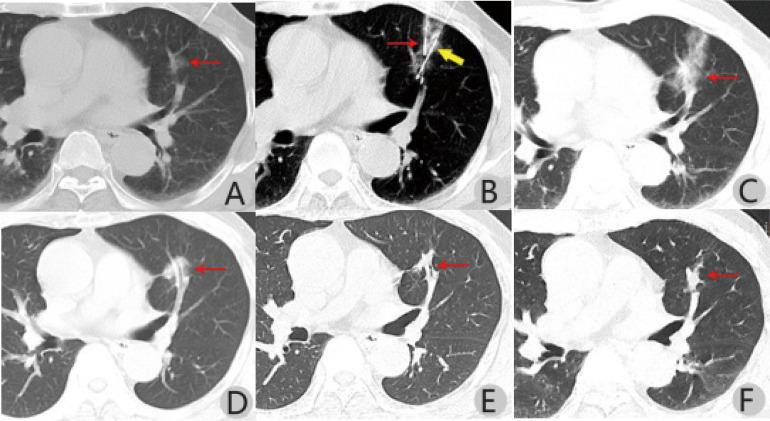

Microwave ablation has become an alternative treatment for pulmonary ground-glass nodules (GGN) and is widely accepted by clinicians. However, its effect on lung function remains unknown. Therefore, this retrospective study aimed to explore pulmonary function changes and associated risk factors in patients undergoing computed tomography (CT)-guided microwave ablation (MWA) for treating pulmonary GGN. Thirty-five patients diagnosed with pulmonary GGN on thin-layer chest CT and enhanced CT were examined. Patients unable or unwilling to undergo thoracoscopic surgery underwent CT-guided simultaneous percutaneous core needle biopsy and MWA. Pulmonary function tests (PFT) were performed before ablation and 3 days and 6 months post-ablation. Forced expiratory volume in one second (FEV1), FEV1%, forced vital capacity (FVC), maximal voluntary ventilation (MVV), and peak expiratory flow (PEF) values pre- and post-MWA were analysed. Linear regression analysis was used to examine the correlation between ablation volume and changes in PFT findings 3 days post-ablation. Associations between patient characteristics, rates of postoperative complications, and PFT findings were analysed. Forty-eight lesions were completely ablated and examined intraoperatively. There were significant differences in pre- and post-operative PFT findings on day 3 but not at 6 months. The mean ablation volume after 3 days of 11.4 ± 6.3 cm was positively correlated with changes in FEV1, MVV, and PEF values. Patients' age (mean, 59.4 ± 13.0 years) positively correlated with changes in PEF values. The rates of change in FVC and MVV values were significantly higher with multiple pulmonary nodules than with isolated pulmonary nodule. PFT findings were similar between patients who experienced or did not experience complications (eg, pneumothorax and pleural effusion). Pulmonary function could be impaired shortly after MWA. PFT findings may correlate with age, ablation volume, and number of ablated lesions. In most patients, pulmonary function returned to the preoperative state after 6 months.

微波消融已成为治疗肺部磨玻璃结节(GGN)的一种替代治疗方法,被临床医生广泛接受。然而,其对肺功能的影响尚不清楚。因此,本回顾性研究旨在探讨 CT 引导下微波消融(MWA)治疗肺部 GGN 患者的肺功能变化及其相关危险因素。

对经薄层胸部 CT 和增强 CT 诊断为肺部 GGN 的 35 例患者进行了检查。对于不能或不愿接受胸腔镜手术的患者,进行 CT 引导下经皮同轴芯针活检和 MWA。在消融前和消融后 3 天和 6 个月进行肺功能检查(PFT)。分析 MWA 前后的 1 秒用力呼气量(FEV1)、FEV1%、用力肺活量(FVC)、最大自主通气量(MVV)和呼气峰流量(PEF)值。采用线性回归分析评估消融体积与 3 天 PFT 检查结果变化之间的相关性。分析患者特征、术后并发症发生率与 PFT 检查结果之间的关系。

48 个病灶完全消融并在术中检查。术后 3 天的 PFT 检查结果与术前有显著差异,但在 6 个月时无差异。术后 3 天的平均消融体积为 11.4±6.3cm,与 FEV1、MVV 和 PEF 值的变化呈正相关。患者年龄(平均 59.4±13.0 岁)与 PEF 值的变化呈正相关。多发肺部结节患者的 FVC 和 MVV 值变化率明显高于孤立性肺部结节患者。有或没有并发症(如气胸和胸腔积液)的患者的 PFT 检查结果相似。

MWA 后肺功能可能会短暂受损。PFT 检查结果可能与年龄、消融体积和消融病灶数量有关。在大多数患者中,肺功能在 6 个月后恢复到术前状态。